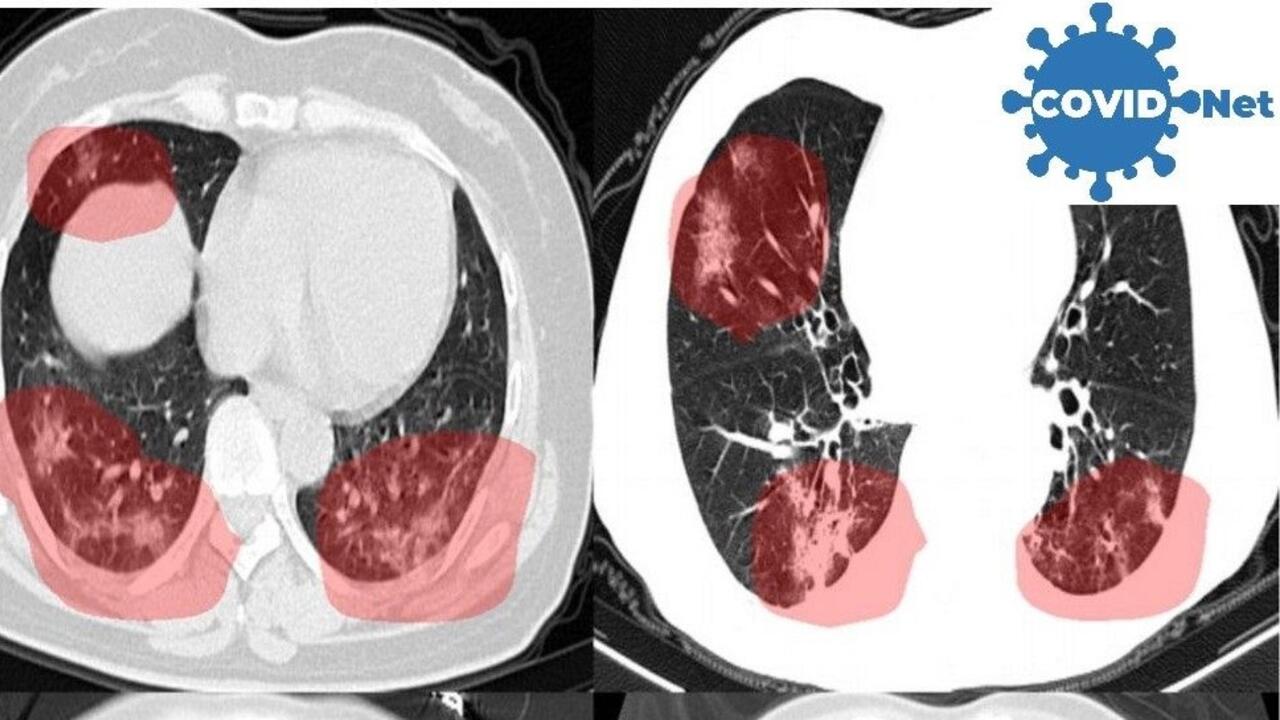

The new AI models, dubbed COVID-Net CT-2, have been found via explainable AI to make their decisions on COVID-19 screening with CT scans using some of the same types of visual cues as expert radiologists.

Photo: CT scans of lungs show areas of concern highlighted in red by new AI models developed by Waterloo Engineering researchers.